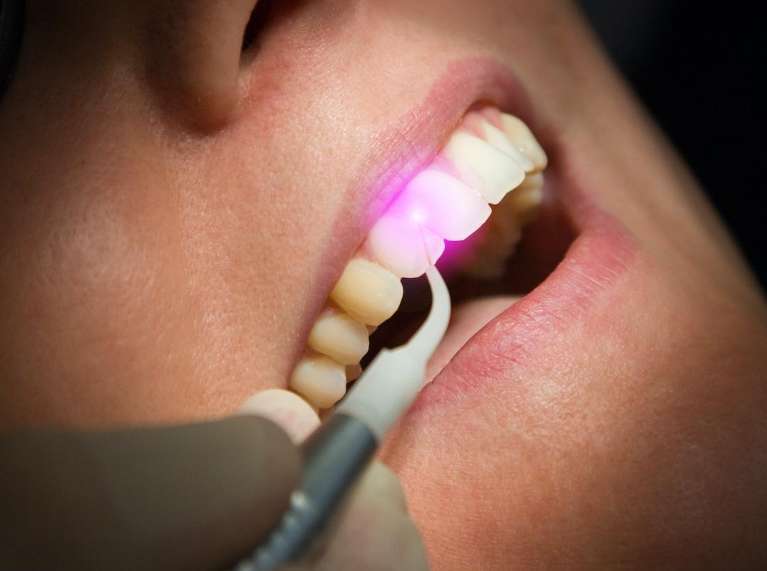

Laser Dentistry

Laser dentistry for soft tissue procedures offers a minimally invasive alternative to traditional surgery. Dr. Klavy can use a precise laser beam to target gum tissue for treatments such as contouring, periodontal therapy, and removing lesions. This technique reduces discomfort, minimizes bleeding, and speeds healing. This means experiencing less anxiety and discomfort during procedures, quicker recovery, and precise, optimal results.